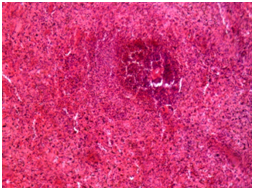

The 7th day of the experiment: In the red pulp there was observed focal accumulations of lymphocytes of various sizes, which gave it patchy appearance. Follicles, marginal zone, PALS of white pulp were expanded and rarefied, were formed by reticulum cells in the state of dystrophy, between of which there were singular lymphocytes, the cells in the state of destruction and macrophages. Extensive extravasations with hemorrhagic impregnation of parenchyma of the lien were revealed in dead animals in the 1st day of the study (Figure 9), and on the 7th day - there was in the parenchyma no division to structural components (red and white pulp) and it consisted of reticular cells, collections of lymphocytes in the state of destruction, between of which there were focuses of pigment, the macrophages (Figure 10).

Figure 10 Spleen, the experimental group, 7 day of the experiment. Hematoxylin and eosin × 100.

In the parenchyma of lien there is no division into structural components (red and white pulp) and it consists of reticular cells, collections of lymphocytes in a state of destruction, between of which there are lobules of pigment, macrophages. The arteries of red and white pulp are sharply narrowed, the wall of homogeneous structure.